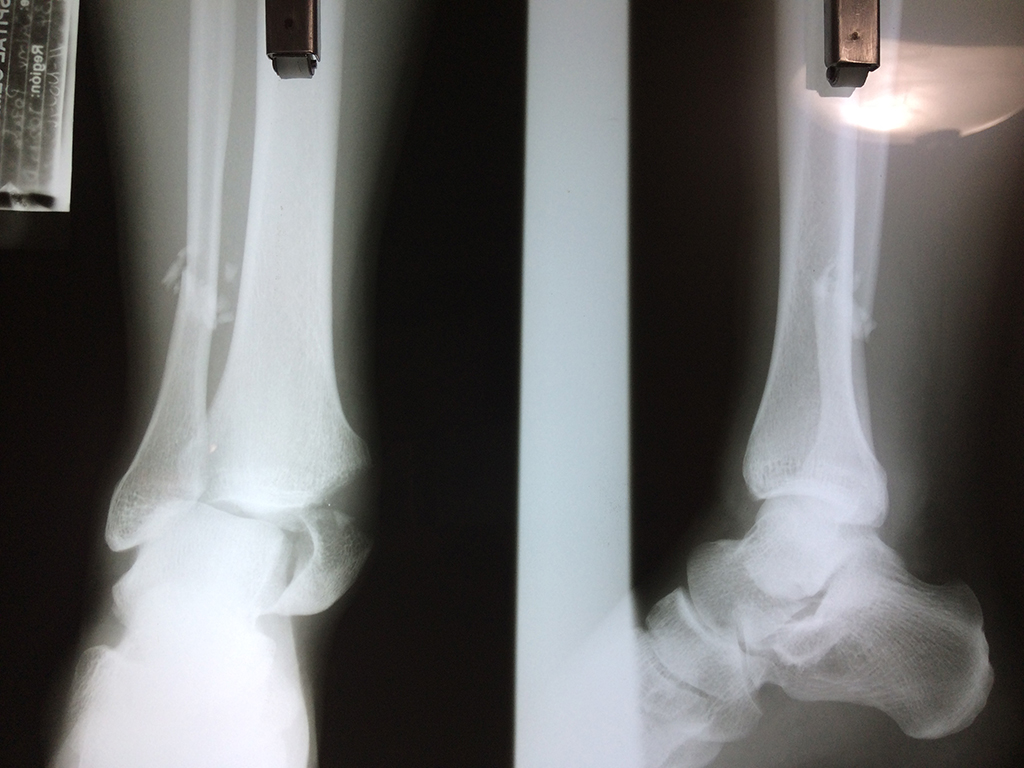

Una fractura de tobillo es la rotura de uno o más de los huesos del tobillo. Estas fracturas pueden ser:

- Producirse en uno o ambos lados del tobillo.

Algunas fracturas de tobillo pueden requerir cirugía si:

- Los extremos de los huesos están desalineados entre sí (desplazados).